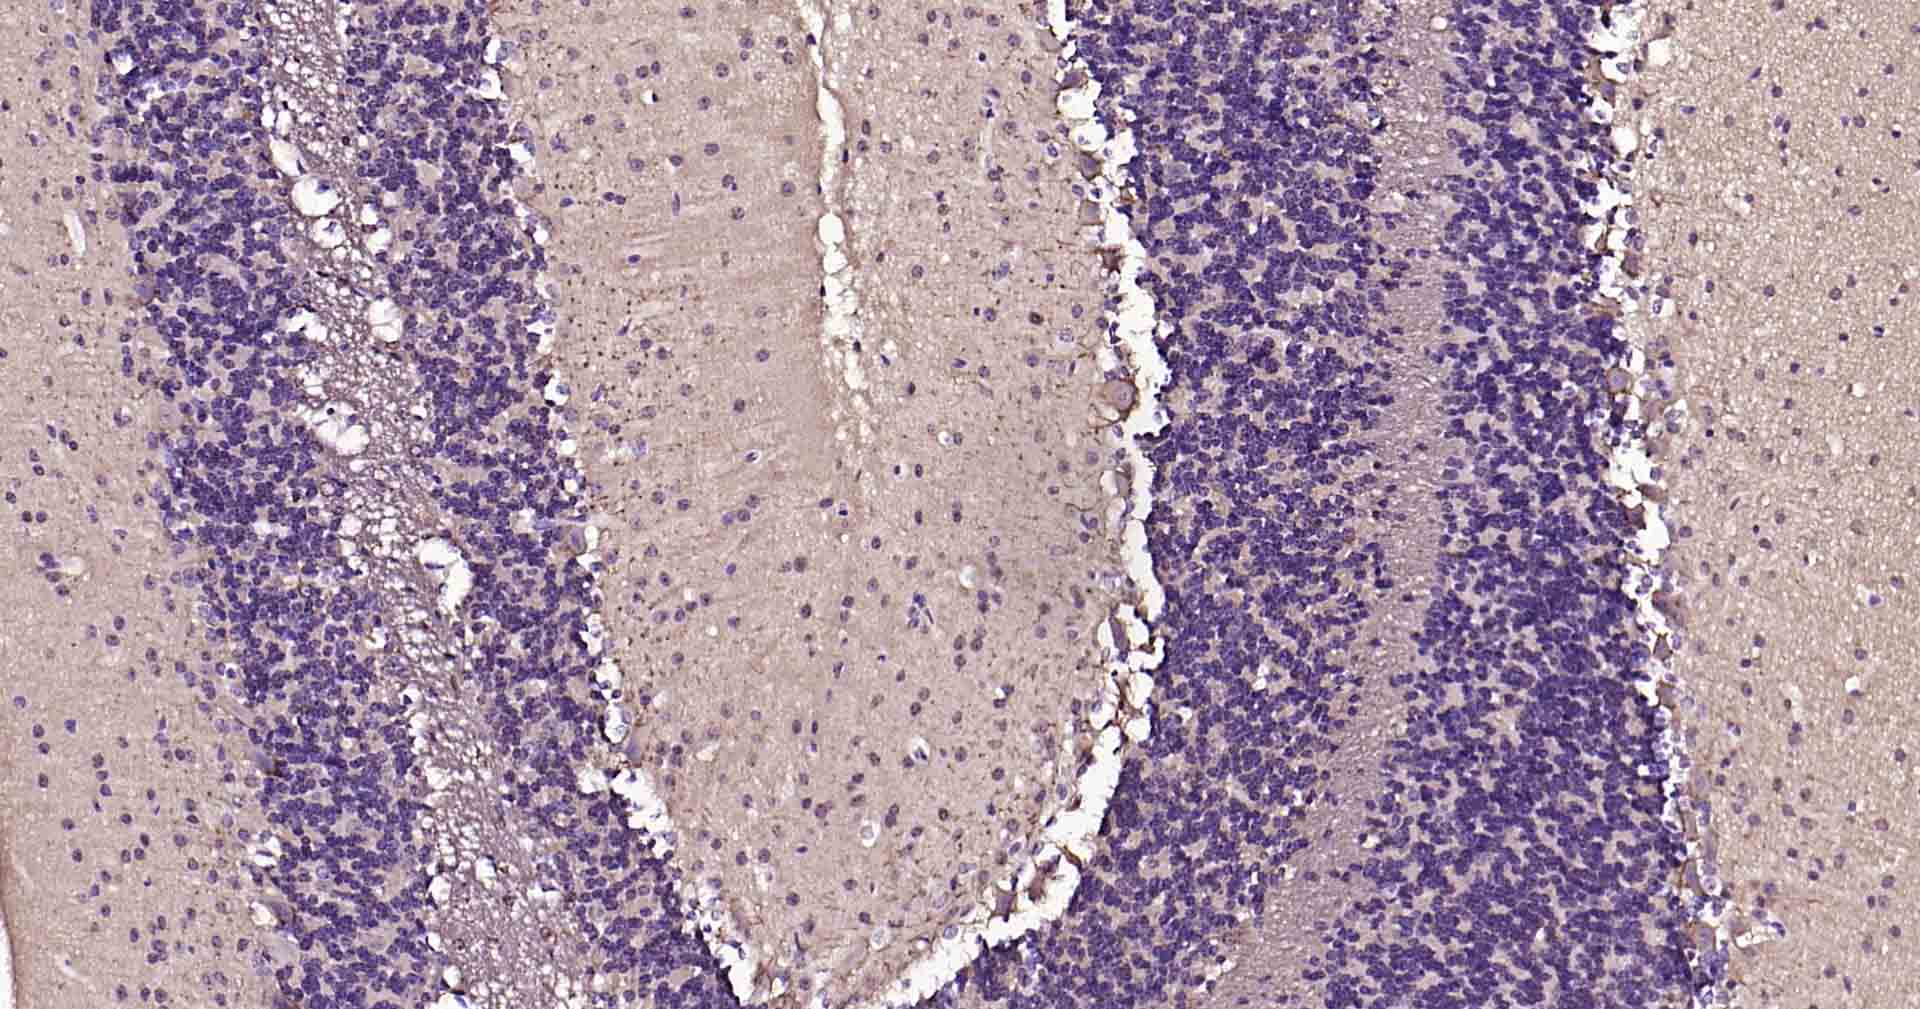

IHC-PHuman, Mouse, Rat1:50-200

IHC-FHuman, Mouse, Rat1:50-200

IFHuman, Mouse, Rat1:50-200